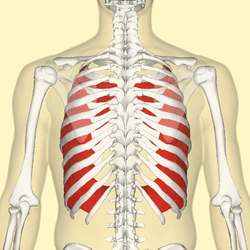

Internal intercostal muscles (red) seen from back. | |

The internal intercostal muscles (intercostales interni) are a group of skeletal muscles located between the ribs. They are eleven in number on either side. They commence anteriorly at the sternum, in the intercostal spaces between the cartilages of the true ribs, and at the anterior extremities of the cartilages of the false ribs, and extend backward as far as the angles of the ribs, hence they are continued to the vertebral column by thin aponeuroses, the posterior intercostal membranes.

Each muscle arises from the ridge on the inner surface of a rib, as well as from the corresponding costal cartilage, and is inserted into the inferior border of the rib above. The internal intercostals are innervated by the intercostal nerve.[1]

Their fibers are also directed obliquely, but pass in a direction opposite to those of the external intercostal muscles.

For the most part, they are muscles of exhalation. In exhalation the interosseous portions of the internal intercostal muscles, (the part of the muscle that is between the bone portion of the superior and inferior ribs), depresses and retracts the ribs, compressing the thoracic cavity and expelling air.[2] The internal intercostals, however, are only used in forceful exhalation such as coughing or during exercise and not in relaxed breathing.[3] The external intercostal muscles, and the intercartilaginous part of the internal intercostal muscles, (the part of the muscle that lies between the cartilage portion of the superior and inferior ribs), are used in inspiration, by aiding in elevating the ribs and expanding the thoracic cavity.[4]